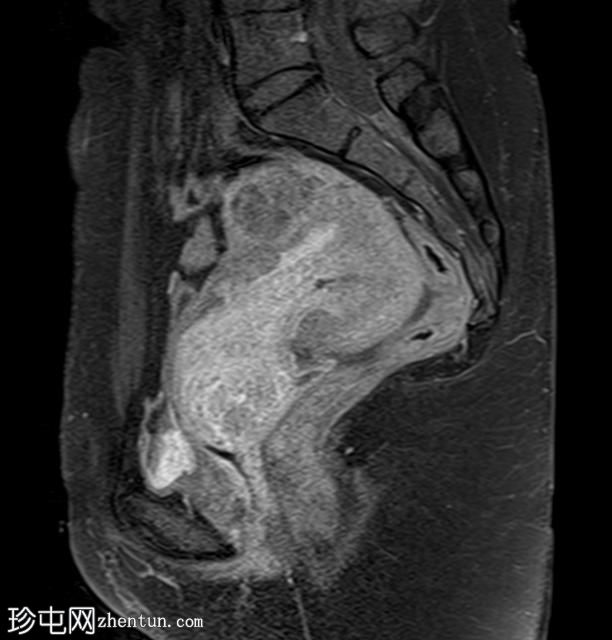

矢状位

T2加权像

子宫增大,前倾后屈,可见多发大小不一、位置各异的壁内肌瘤(主要位于Figo 2、5和6区)。

一个边界清晰的带蒂宫腔内肿块经扩张的宫颈管脱出。T1加权像上呈等信号,T2加权像上呈中低信号,周围环绕着高信号的子宫内膜,静脉注射对比剂后呈明显不均匀强化。

MRI 影像特征最符合带蒂子宫肌瘤经扩张的宫颈管脱垂,并伴有多个子宫肌瘤。